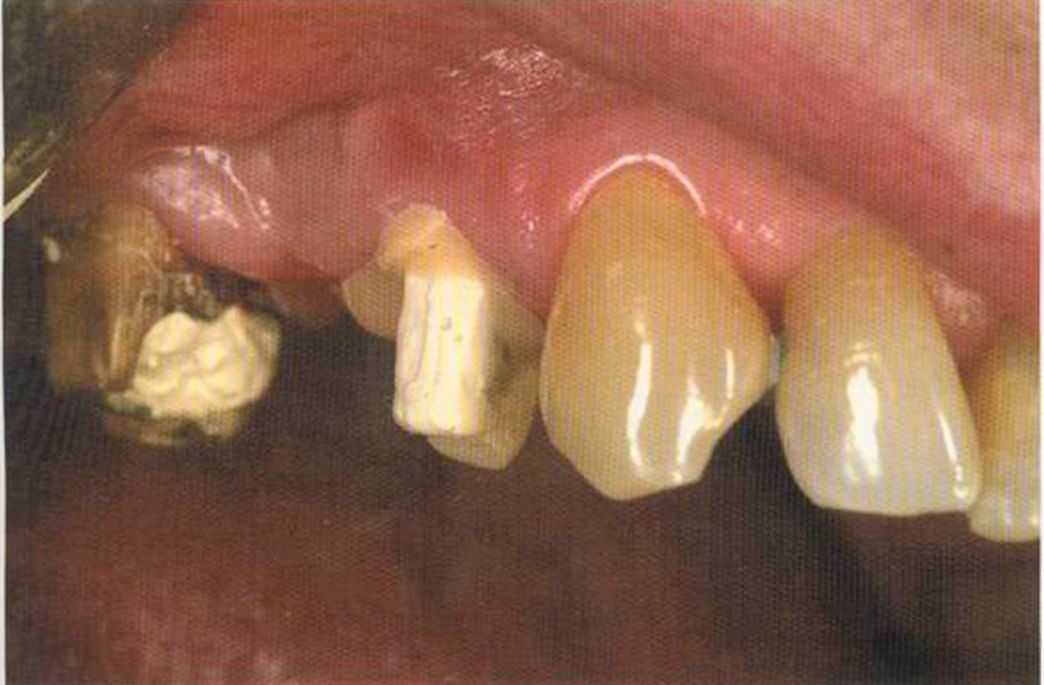

Теперь штифт окончательно отпрепарирован. Можно снимать оттиск. В этом случае мы изготовим цельнокерамический мостовидный протез из Zirconia.

Штифт на 14 зафиксирован на цемент Panavia ТС.

Соотношение размеров готовых вкладок и спички. Они маленькие, но требуют много работы и могут быть очень полезны пациенту.

Вкладки все еще выглядят очень грубо. После фиксации в полости рта их надо препарировать.